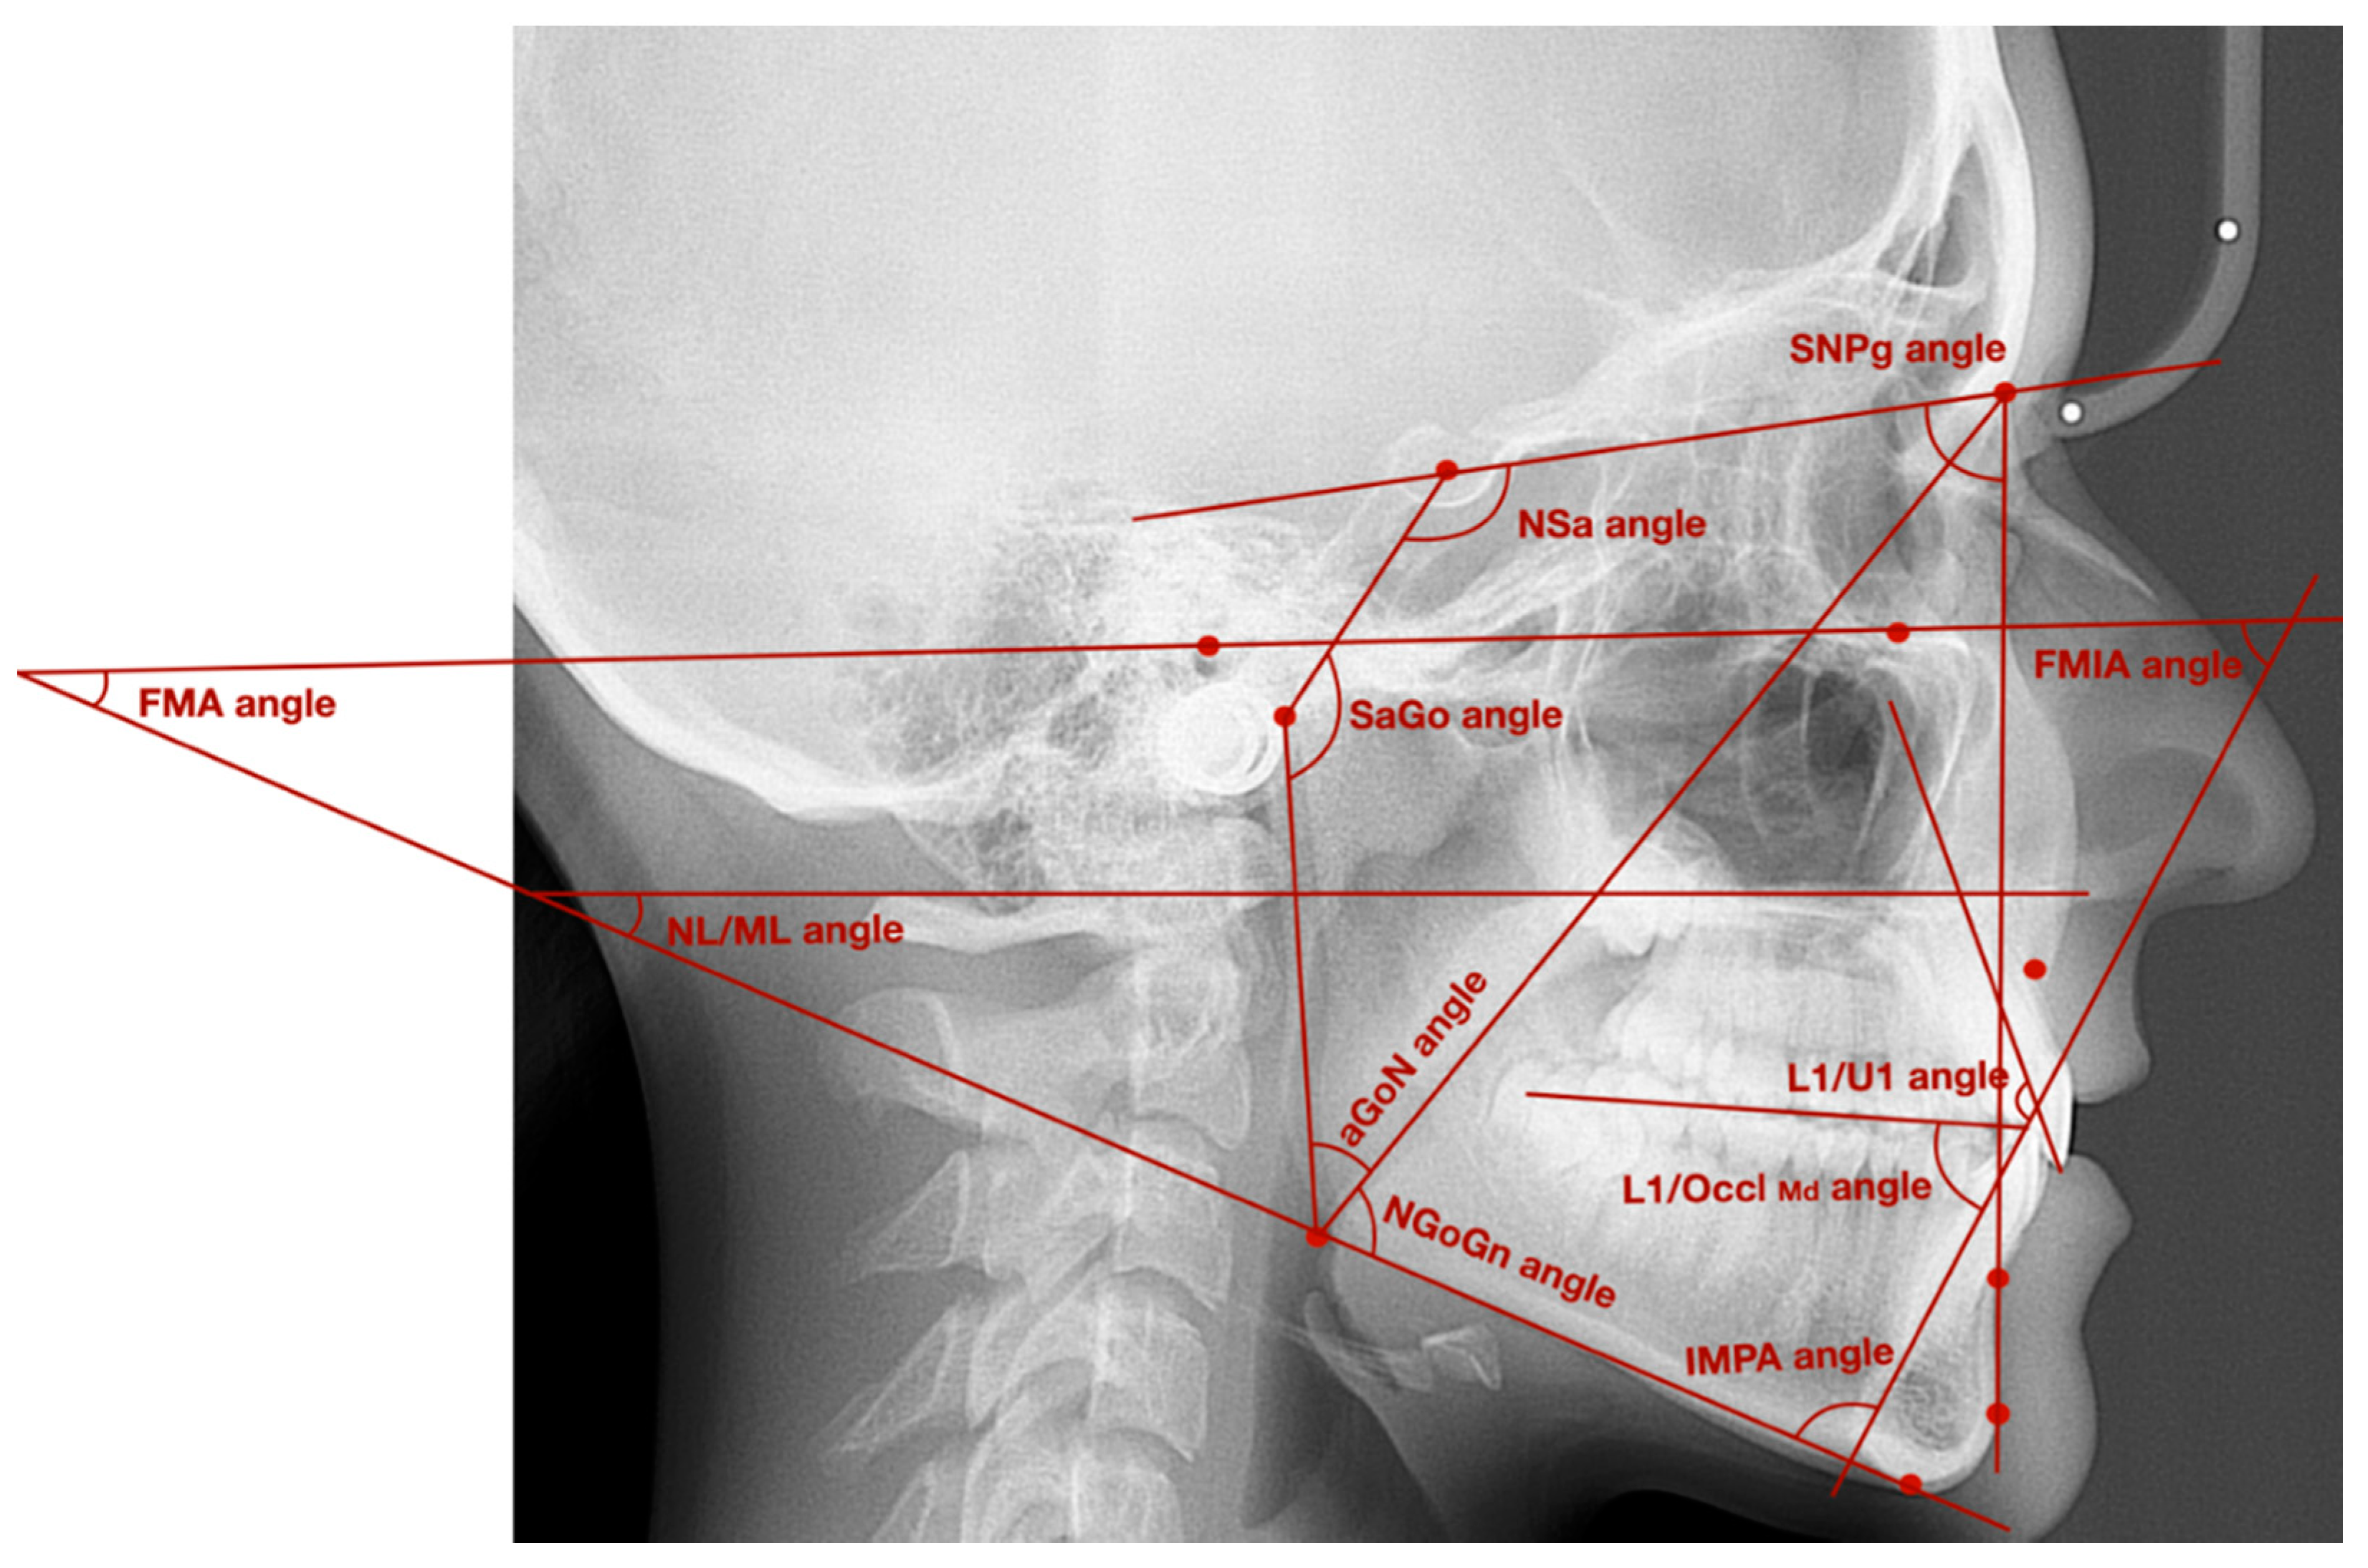

| Points/Lines/Angles | Description of Points/Lines/Angles |

|---|---|

| Point S | Sella—geometrical center of Sella turcica |

| Point N | Nasion—the most anterior point localized in the frontonasal suture |

| Point Go | Gonion—point localized at the intersection of mandibular line and line tangent to the posterior border of mandibular ramus |

| Point a | Articulare—point localized at the intersection of sphenoid bone base and the posterior part of condylar outline |

| Point Po | Porion—the most superior part of external acoustic opening |

| Point Or | Orbitale—the most inferior point localized in the lower margin of the orbit |

| Point A | Subspinale—the deepest point localized in the anterior outline of the maxilla, below the anterior nasal spine |

| Point B | Supramentale—the deepest point localized in the anterior outline of the mandible, above the pogonion |

| Wits | AO-BO—the distance between the perpendicular projection of points A and B onto the functional occlusal plane |

| Point Pg | Pogonion—the most prominent point localized in the osseous outline of mental tuberosity |

| NL line | Nasal line—line between anterior and posterior nasal spines |

| ML line | Mandibular line—line between gnathion and the lowest point localized in the masseteric tuberosity (also known as GoGn line) |

| FH line | Frankfort horizontal line—line between points: porion and orbitale |

| L1 line | Long axis of lower incisor—line which connects the incisal edge with the radiological apex of lower incisor |

| U1 line | Long axis of upper incisor—line which connects the incisal edge with the radiological apex of upper incisor |

| OcclMd | Mandibular occlusal plane—line which connects the anterior cusp tips of lower first molars with the incisal edges of the lower central incisors |

| SN line | Sella-nasion line—line of anterior cranial base, which connects points: nasion and sella |

| Sa line | Line which connects points: sella and articulare |

| aGo line | Line which connects points: articulare and gonion |

| NGo line | Line which connects points: nasion and gonion |

| NPg line | Line which connects points: nasion and pogonion |

| SNPg angle | Angle between SN line and NPg line |

| NL/ML angle | Angle between NL line and ML line |

| FMA angle | Angle between FH line and ML line |

| FMIA angle | Angle between FH line and long axis of lower incisor |

| IMPA angle | Angle between long axis of lower incisor and ML line |

| L1/U1 angle | Interincisal angle—angle between long axes of lower and upper incisors |

| L1/OcclMd angle | Angle between long axis of lower incisor and mandibular occlusal plane |

| NSa angle | Saddle angle—angle between SN line and Sa line |

| SaGo angle | Articular angle—angle between Sa line and aGo line |

| aGoGn angle | Gonial angle—angle between aGo line and GoGn line |

| aGoN angle | Upper gonial angle—angle between aGo line and NGo line |

| NGoGn angle | Lower gonial angle—angle between NGo line and GoGn line |

| Analysis of Morphology and Position of the Mandible and Position of the Mandibular Incisors | Measurement |

| Skeletal class | Wits analysis |

| Sagittal position of the mandible | SNPg angle NSa angle SaGo angle |

| Vertical position of the mandible | FMA angle NL/ML angle |

| Angle of the mandible | aGoGn angle |

| Inclination of mandibular ramus | aGoN angle |

| Inclination of mandibular corpus | NGoGn angle |

| Position of the mandibular incisors | FMIA angle IMPA angle L1/OcclMd angle L1/U1 angle |